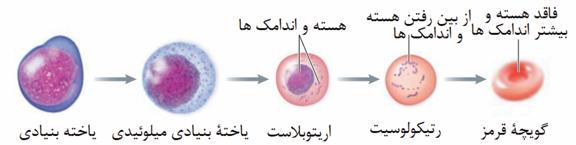

الف) مواد مفید موثر در روند انعقاد را دوباره به خون بازمیگرداند.

الف) موادی مانند یون کلسیم برای انعقاد ضروریاند. کلیه با بازجذب کلسیم به حفظ هم ایستایی آن در بدن و فرایند انعقاد خون کمک میکند.